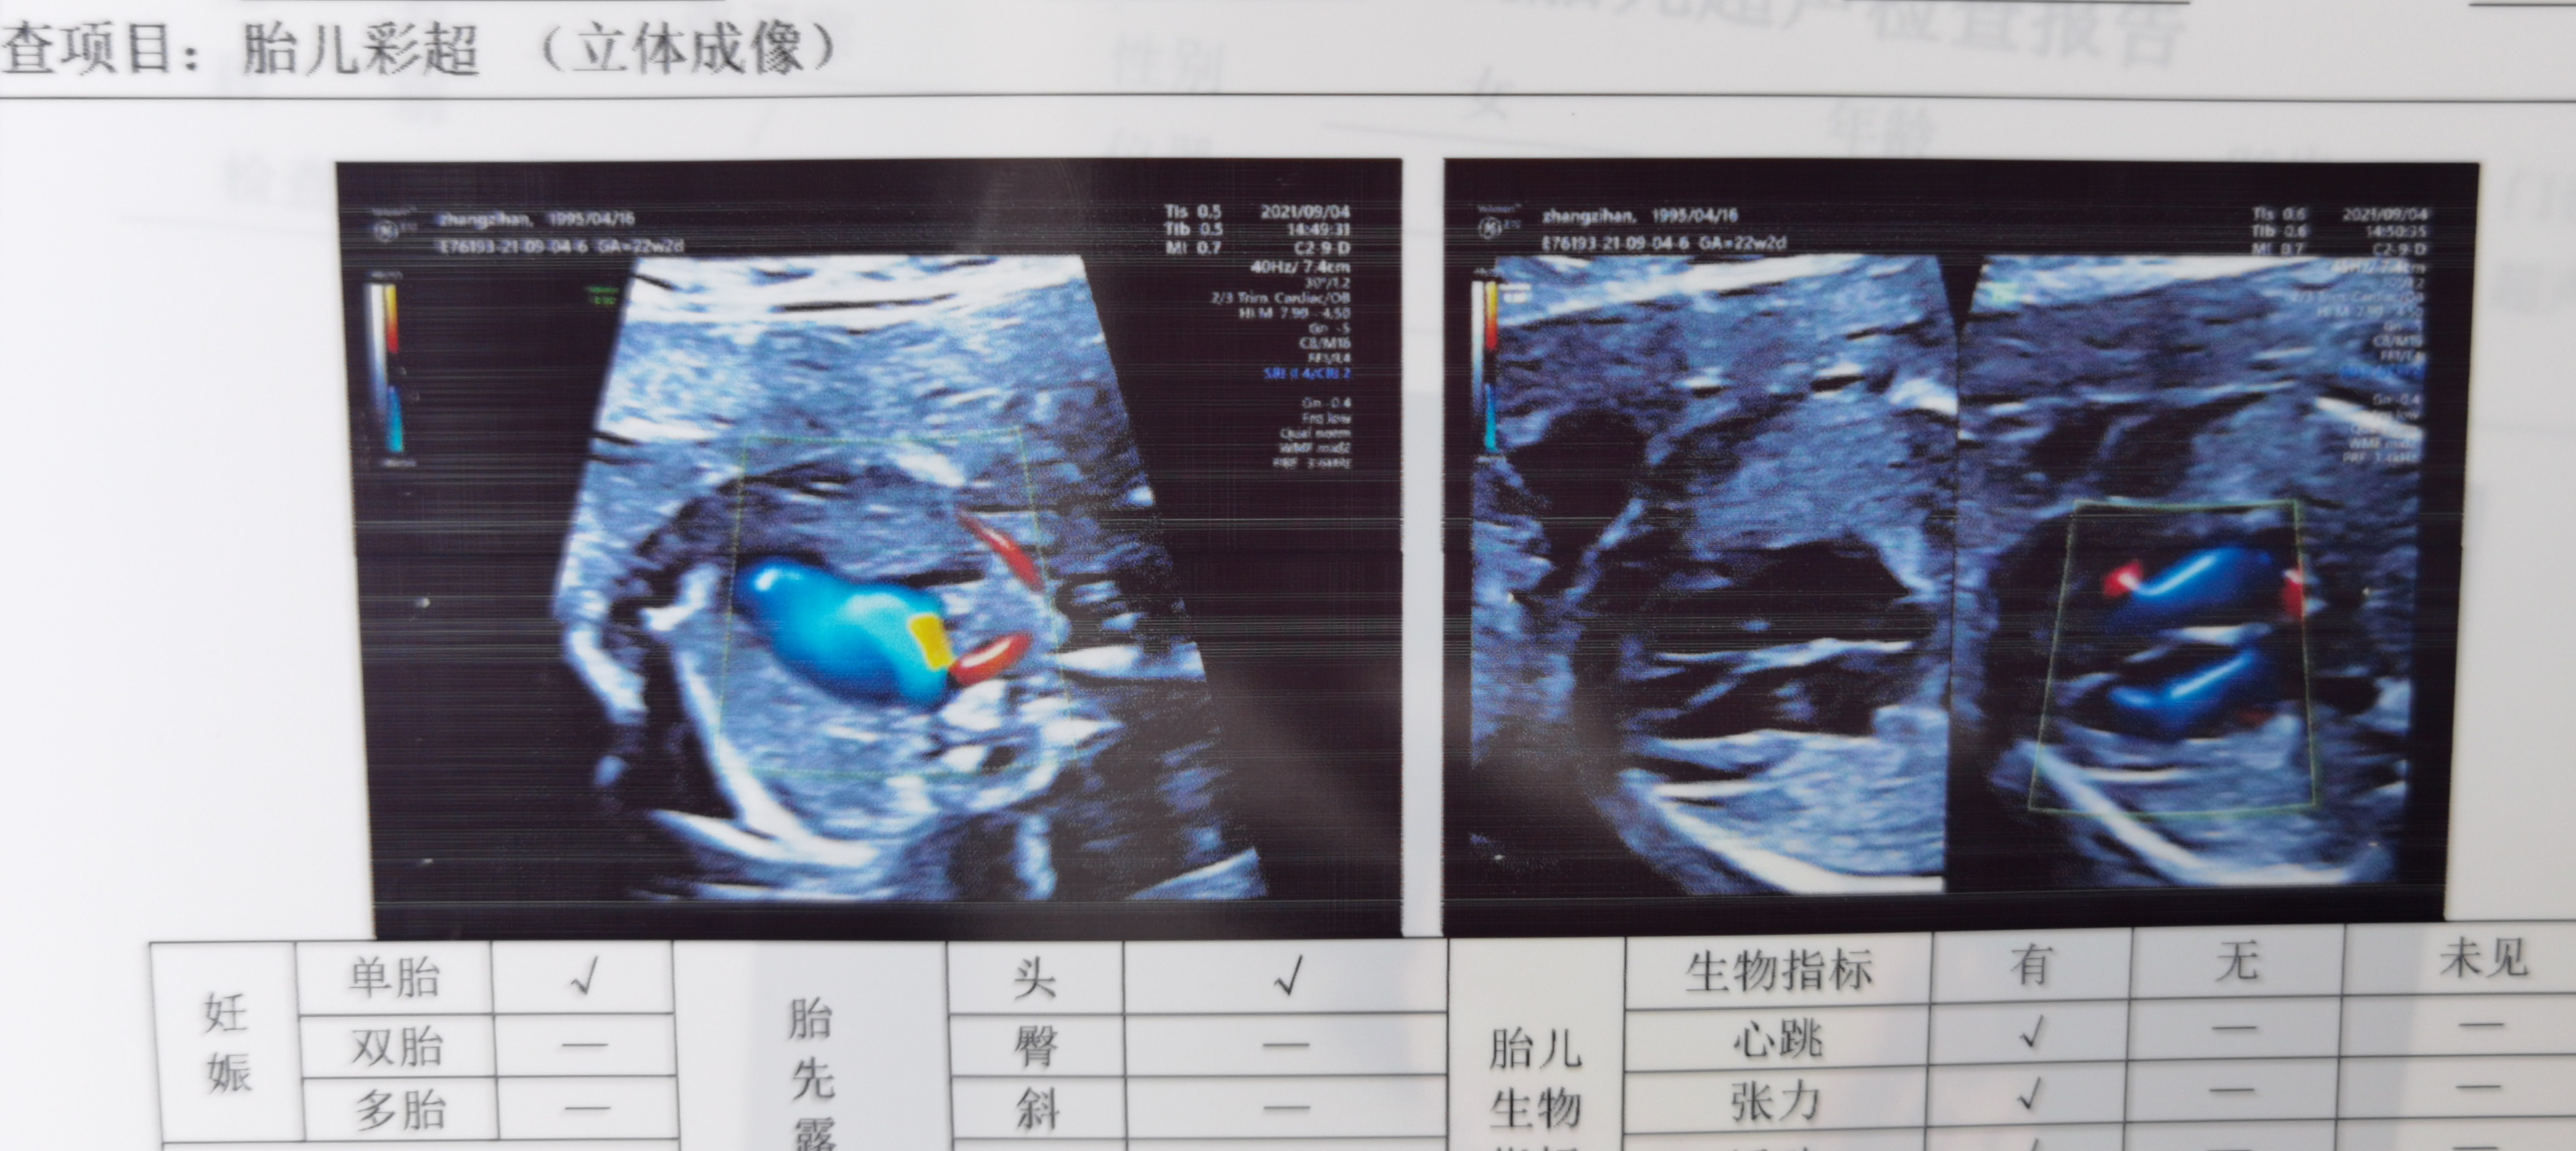

“可见右侧锁骨下动脉绕过气管后方自降主动脉发出,胎儿右侧锁骨下动脉迷走,建议优生遗传及产科咨询,复查”,家住华容的小张,怀孕5个月做四维彩超时,拿到报告单医生建议复查,她感觉天都塌下来了。

担心宝宝有问题,她茶饭不思眼泪止不住往下掉,经好友介绍,找到超声网络达人“超人徐班长”武汉市第四医院超声科徐琦医生。徐琦仔细查看了小张带来的一些检查单据,宝宝各项数据都是正常的,染色体检查和心脏彩超也显示没有问题,只是单纯的“右锁骨下动脉迷走”,并不会对宝宝有什么影响。小张这才解开心结,放松心情。

二、锁骨下动脉迷走

锁骨下动脉迷走是主动脉弓最常见的一种变异,在健康成人中的发生率高达0.5%-1.4%。因此,单纯的锁骨下动脉迷走相当于告诉你宝宝是个与众不同的健康孩子,没什么好担心的。与之类似的情况还有“右脐静脉”、“单脐动脉”等。